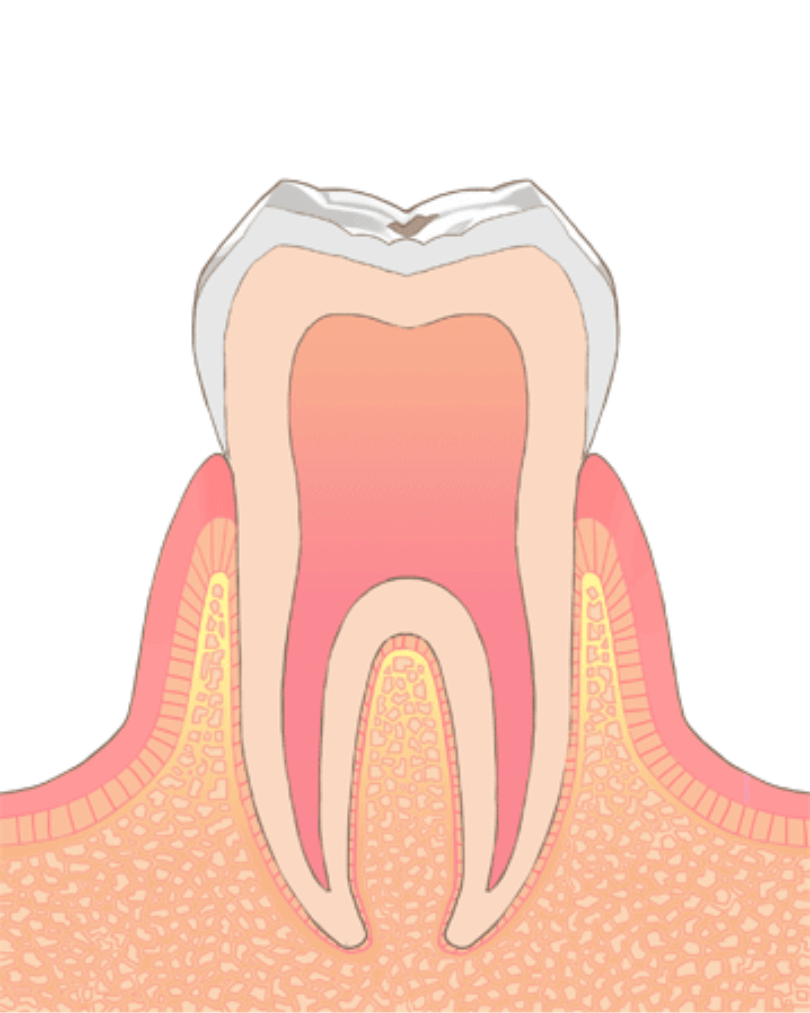

やや大きい虫歯(C2:象牙質まで進行)

虫歯が大きくなり、象牙質(歯の内側の層)にまで進行してしまっている場合には、コンポジットレジン治療に加え、歯を削った部分の歯型を取ってつめ物をする「インレー(アンレー)治療」も選択肢として出てます。

また、虫歯の進行具合に応じて、虫歯を除去後、神経を保護する処置をして、経過観察する事もあります。

治療には2回~3回程度の通院が必要な事が多いです。